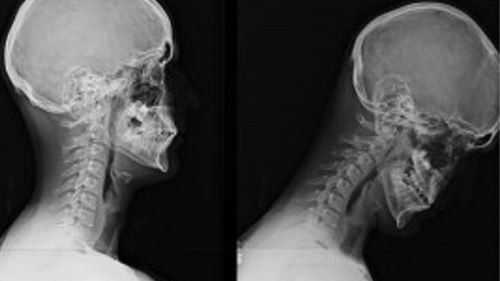

Istilah “Text Neck” digunakan oleh pakar kesihatan untuk menggambarkan kesakitan kronik di bahagian leher dan bahu akibat terlalu kerap tunduk melihat skrin telefon atau komputer.

Postur kepala yang menunduk untuk membaca mesej atau menatap media sosial menyebabkan otot leher bekerja lebih keras daripada biasa. Lama-kelamaan, ia boleh membawa kepada:

- Kerosakan tulang belakang serviks.